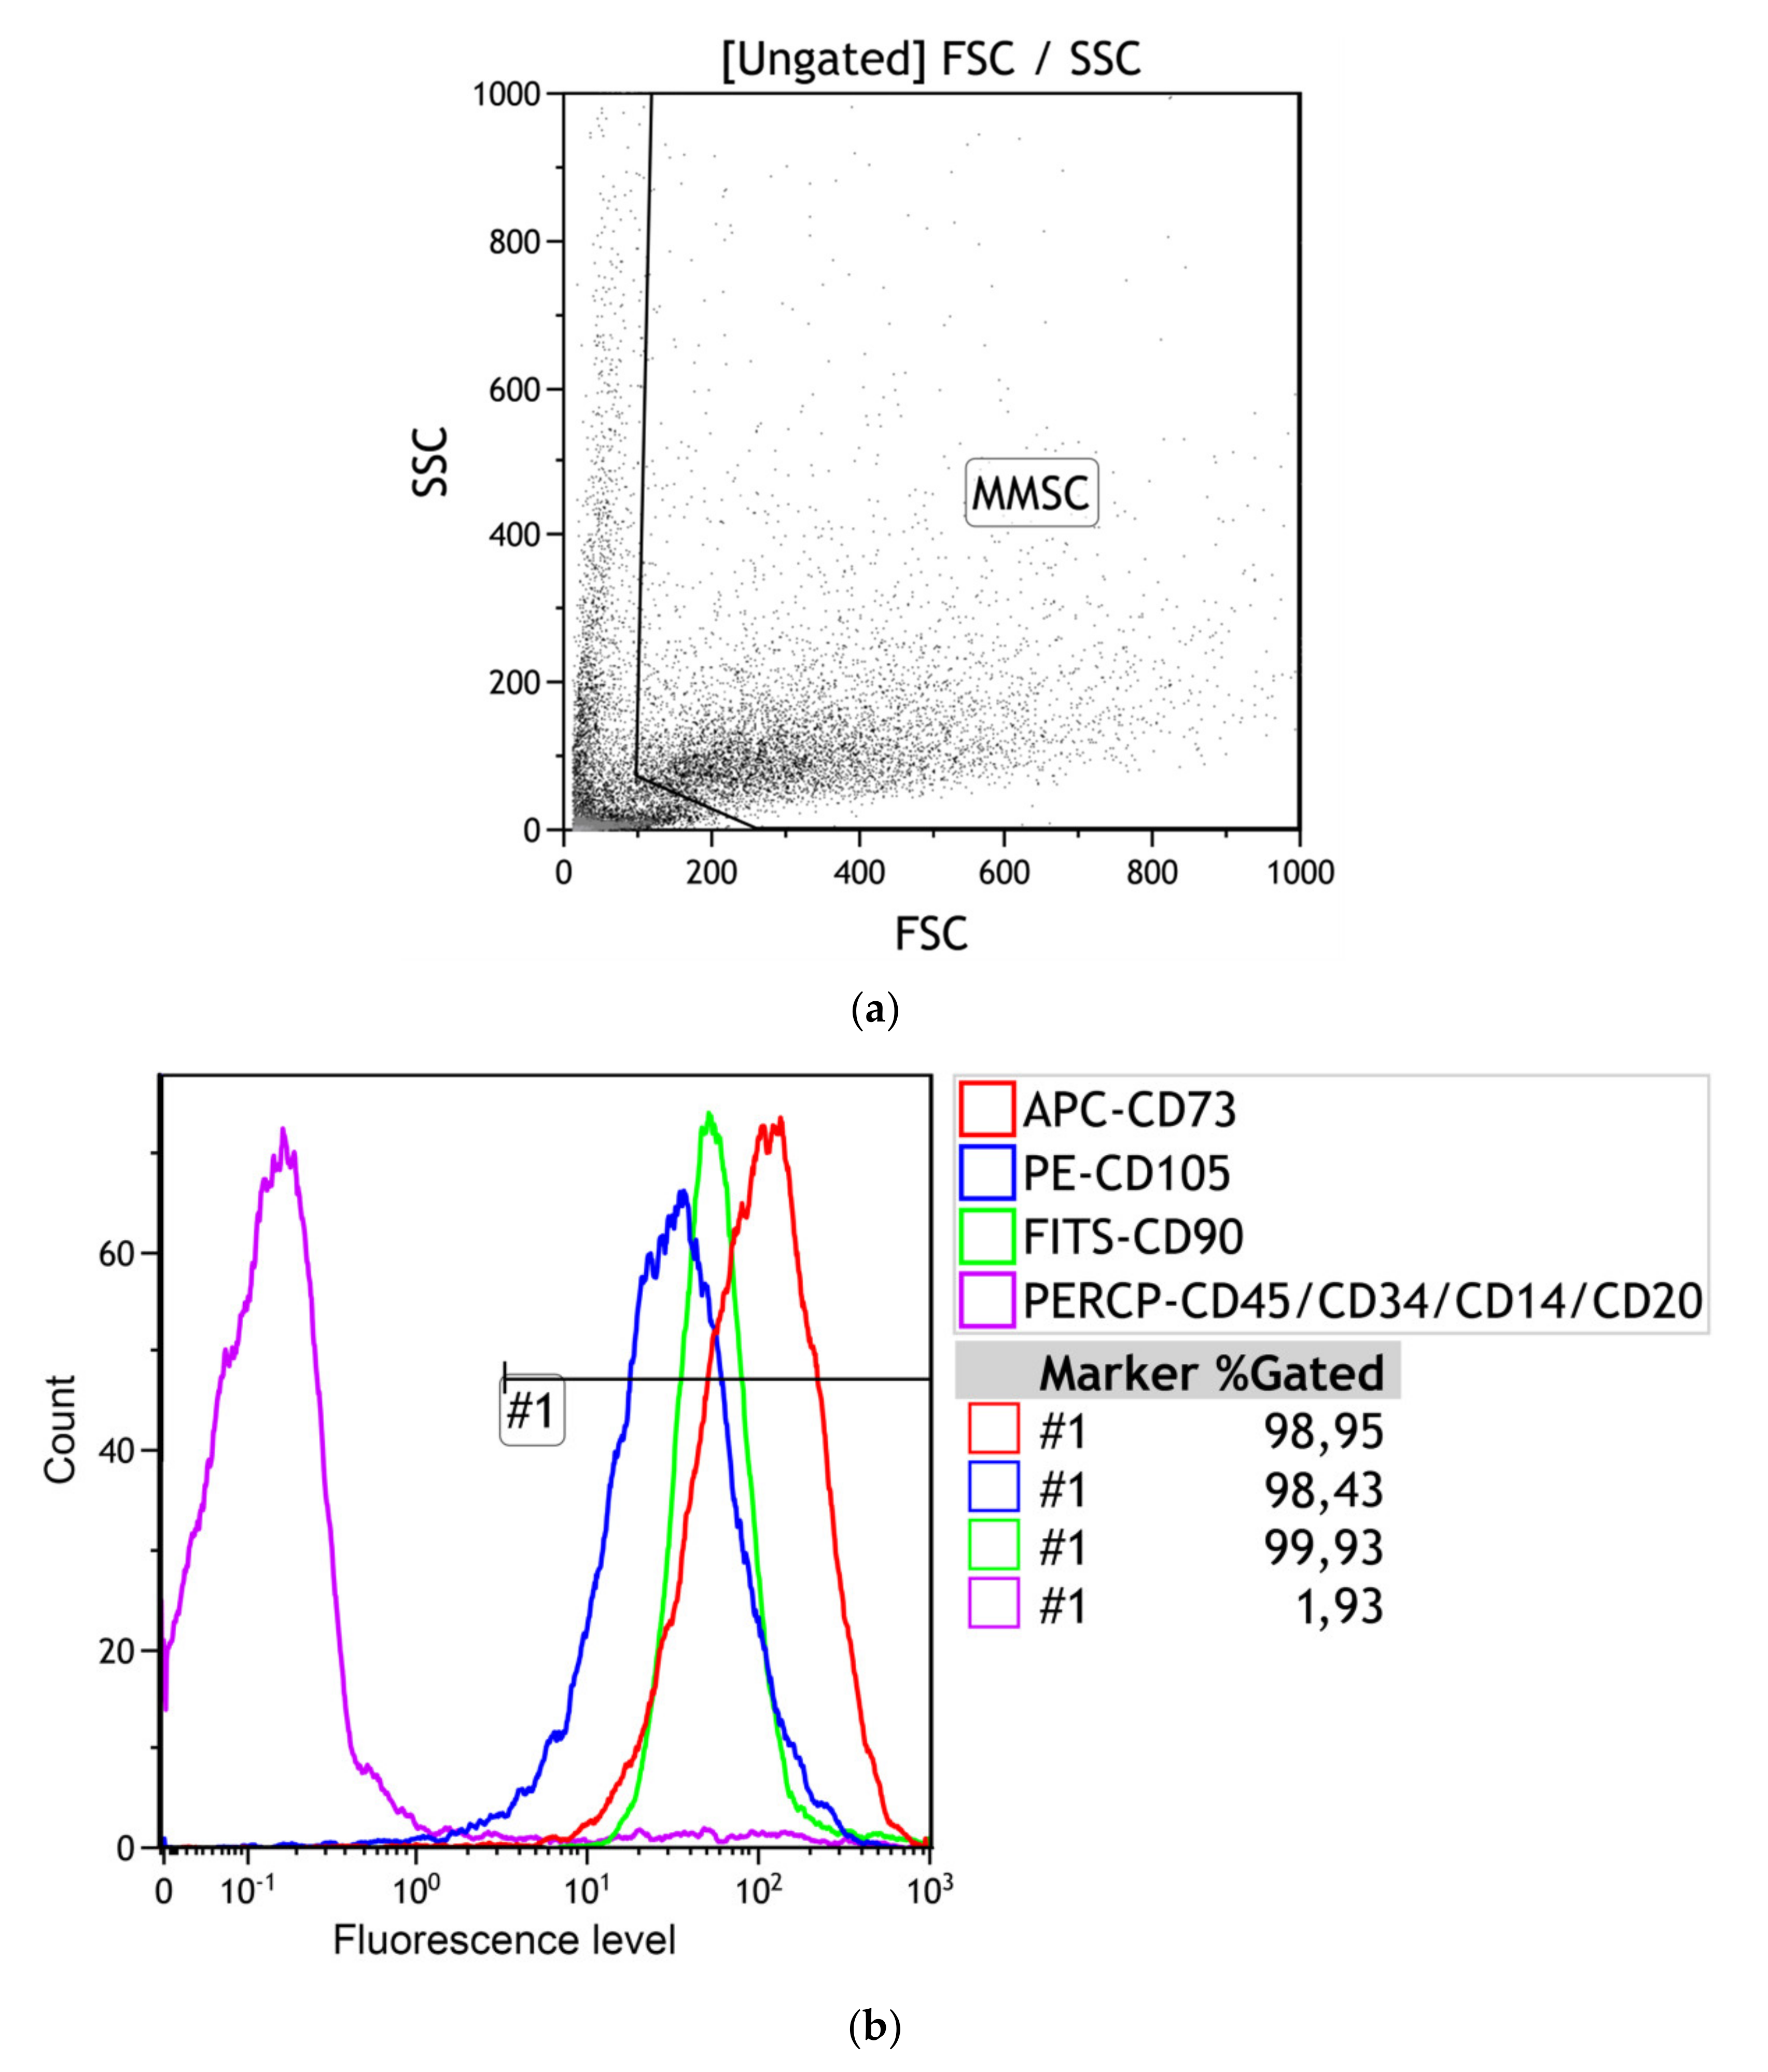

3.2.1. Multilineage Nature of hAMMSC Culture

| Stromal Cell Markers, % | Hematopoietic Cell Markers, % | ||

|---|---|---|---|

| CD73 | CD90 | CD105 | [CD45, 34, 20, 14] |

| 98.46 (98.36–98.95) | 98.57 (98.09–99.93) | 98.91 (98.43–99.05) | 1.34 (1.26–1.93) |